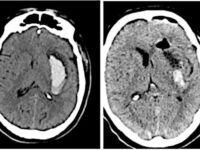

Виды медико-хирургической помощи